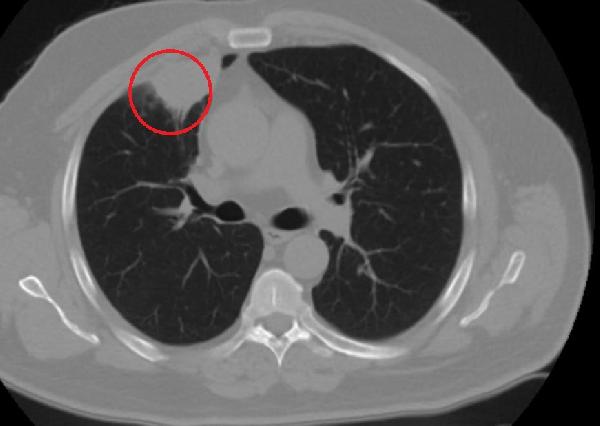

Ameliyat öncesi N.T.'nin Covid-19 testi pozitif çıkınca operasyon ertelendi. Koronavirüs tedavisine başlanan N.T.'nin son testi negatif çıktı. Dr. Fatoş Kozanlı, tedavi sonrası tomografisi çekilen N.T.'nin akciğerindeki tümörün yok olduğunu gördü. Kozanlı, N.T.'nin kendilerine başvurduğunda koronavirüs belirtisi olmadığını ancak ameliyat öncesi PCR testi yaptıklarını söyledi. Koronavirüs tedavisinin ardından ortaya çıkan sonucun kendisini de şaşırttığını belirten Kozanlı, şunları söyledi:

"Hastamız, çalıştığı başka bir kentte göğsünden darbe alıyor ve ağrıları geçmeyince bir üniversite hastanesine başvuruyor. Burada hastaya bir akciğer grafisi çekiliyor. Sağ akciğerinde bir kitleye rastlanıyor. Daha sonra hastaya, bir akciğer tomografisi çekiliyor ve göğüs cerrahisi için önemli büyüklükte olan 4 santimetre çapında, akciğer kanserine benzer özellikte radyolojik bulgular olan bir kitle tespit ediliyor. Daha sonra hastaya yapılan ileri tetkiklerde akciğer kanseri teşhisi konuluyor. Hastaya bir cerrahi planlanıyor. Hasta Kahramanmaraşlı olduğu için kendi memleketine gelmeyi tercih ediyor. Bize başvurdu ve göğüs ağrısı şikayeti vardı. Öksürük, nefes darlığı, balgam çıkarma, ateş gibi şikayetleri yoktu. Hastayı biz de değerlendirdik ve ameliyat olmasına karar verdik. Çünkü akciğer kanserine çok benzer radyolojik bulguları vardı. Sağlık Bakanlığımızın kuralları gereği her hastayı ameliyat öncesi PCR testi yapılır. Biz de ameliyat gecesi hastadan PCR testi aldık ve testi pozitif geldi. Ameliyatımızı 14 gün erteledik ve hastamıza koronavirüs tedavisi uygulandı. Hasta 14'üncü gün tekrar bize başvurdu ve yapılan PCR testi negatif çıktı. Yeni bir tomografi çektik ve tümörün tamamen ortadan kalktığını gördük. Şimdi sonuç bilgilerinden başlangıca gittiğimizde, bu bir akciğer kanseri olsaydı, ortadan kalkması mümkün değildi. Başka bir patolojiye bağlı durum olsaydı, yine verdiğimiz tedaviyle ortadan kalkmasını çok beklemeyiz. Antiviral tedavisi verdik ve hastanın radyolojik bulguları neredeyse tamamen normale döndü. Hastaya bunu izah ettik, 'Dünya literatüründe hiç görülmeyen bir radyolojik bulgu' diyerek. Bu gördüğümüz manzara artık hastanın akciğer grafisinde yok, akciğer kanseri değil. "